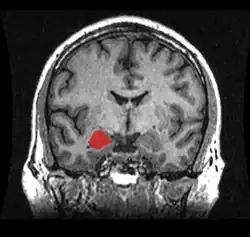

Nos mamíferos, o hipotálamo e substância cinzenta periaquedutal do mesencéfalo estão entre as áreas envolvidas no comportamento agressivo, especialmente uma estrutura integrante do sistema límbico denominada amígdala.[15]

As bases neurais da agressão têm sido consistentemente estabelecidas nos últimos anos, onde regiões cerebrais e neurotransmissores, bem como as suas ligações com diversos genes, hormônios e transtornos psiquiátricos, têm sido triadas.[3][7] Dentre as estruturas corticais, o Córtex Pré-Frontal (CPF) é a região cerebral mais amplamente associada com a agressão impulsiva em humanos. O CPF desempenha um papel central no controle de comportamentos, no direcionamento a metas e na tomada de decisões. Pacientes com lesões no CPF ventromedial (CPFvm) tiveram uma maior probabilidade de mostrar confrontos verbais e agressividade, se comparados com pacientes com lesões em outras áreas cerebrais e com grupo-controle sem lesões.[19] Homens com transtorno de personalidade antissocial têm mostrado alterações no COF, no Córtex Cingulado Anterior (CCA), na Insula e na Amígdala. Similarmente, pacientes com Transtorno de Personalidade Borderline e Transtorno Explosivo Intermitente também apresentam características de funcionamento atípico nessas regiões. Estudos de neuroimagem têm confirmado uma disfunção e redução no volume do COF, CCA e CPFvm em pessoas com comportamento agressivo.[20][3]

Um número crescente de evidências tem corroborado a função da amígdala como uma das regiões cerebrais mais importantes para agressão na espécie humana. A amígdala, envolvida no processamento de estímulos biologicamente relevantes e reações emocionais, e o CPF, são reciprocamente conectados.[7][3][20] Além disso, neurotransmissores como serotonina, GABA e dopamina, e hormônios como testosterona, progesterona, cortisol e vasopressina, apresentam um relevante papel determinante para a manifestação do comportamento agressivo.[3]